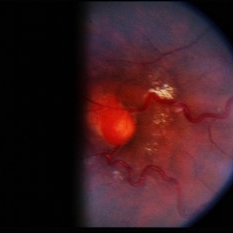

Retinal Capillary Hemangioblastoma

Retinal capillary hemangioblastoma associated with Von Hippel-Lindau Disease. No history. Dilated tortuous vessel and hemorrhage is shown.

Condition/keywords: retinal capillary hemangioblastoma, Von Hippel-Lindau